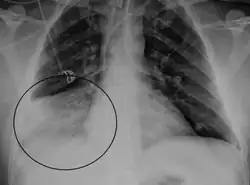

.png)

The identification of HMPV has predominantly relied on reverse-transcriptase polymerase chain reaction (RT-PCR) technology to amplify directly from RNA extracted from respiratory specimens. Alternative more cost-effective approaches to the detection of HMPV by nucleic acid-based approaches have been employed and these include: